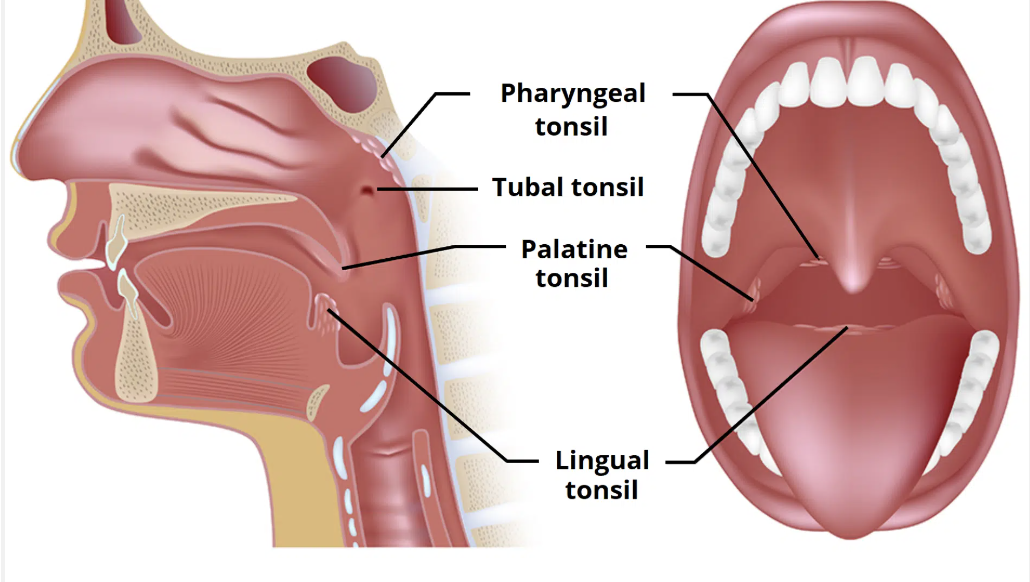

tonsils: state the groups of tonsillar tissue

4 groups of tonsillar tissue

palatine tonsils - paired

pharyngeal tonsils/ adenoids - unpaired

lingual tonsils - paired

tubal tonsils - paired

tonsils: palatine tonsils location

palatine tonsils location

between the palatoglossal (anterior) and palatopharyngeal (posterior) arches

oropharynx

tonsils: pharyngeal tonsils/ adenoids location

pharyngeal tonsils/ adenoids location

the posterior wall of the nasopharynx

tonsils: lingual tonsils location

lingual tonsils location

underneath the mucosa of the posterior 1/3 of tongue

tonsils: tubal tonsils location

tubal tonsils location

around the entrance to the auditory/ Eustachian tube

MAY OR MAY NOT BE PRESENT